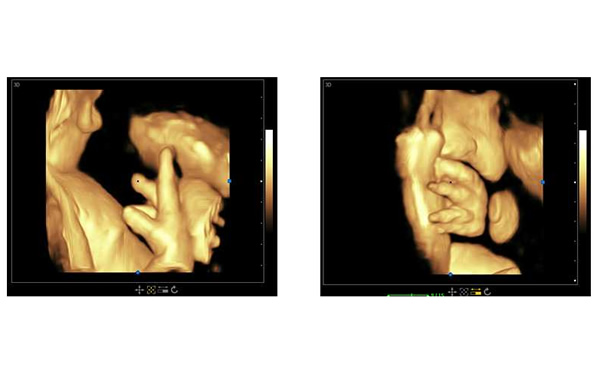

孕期B超檢查三個階段,大為醫(yī)療高端彩超孕期胎兒顯示

懷孕中期,通過B超檢查可以大概知道子宮內(nèi)的胎兒生長的情況。并且可以通過B超了解到孩子的身體組織器官有沒有畸形。如果孩子出現(xiàn)了畸形,根據(jù)醫(yī)生的建議或者是相關(guān)的規(guī)定來決定是不是不再繼續(xù)妊娠。

這個時候做B超就可以了解到子宮內(nèi)羊水的含量,孕婦體內(nèi)的胎盤是不是處于正常的狀態(tài),以及孩子有沒有出現(xiàn)臍帶繞頸的情況。如果子宮內(nèi)的羊水不夠,胎盤出現(xiàn)鈣化的情況,或者孩子出現(xiàn)了臍帶繞頸的現(xiàn)象,那么就要加以重視,好好咨詢醫(yī)生。B超還可以知道胎兒頭徑的多少以及胎兒骨骼的生長情況,以此來大概判斷出孩子到底有多重,準(zhǔn)確得知胎寶寶的在子宮中的位置,并判斷孩子是不是可以自然生產(chǎn)出來。此外,B超檢查還可以知道胎兒臍帶血流參數(shù),通過此參數(shù)可以知道胎兒在子宮內(nèi)是不是正常地生長。